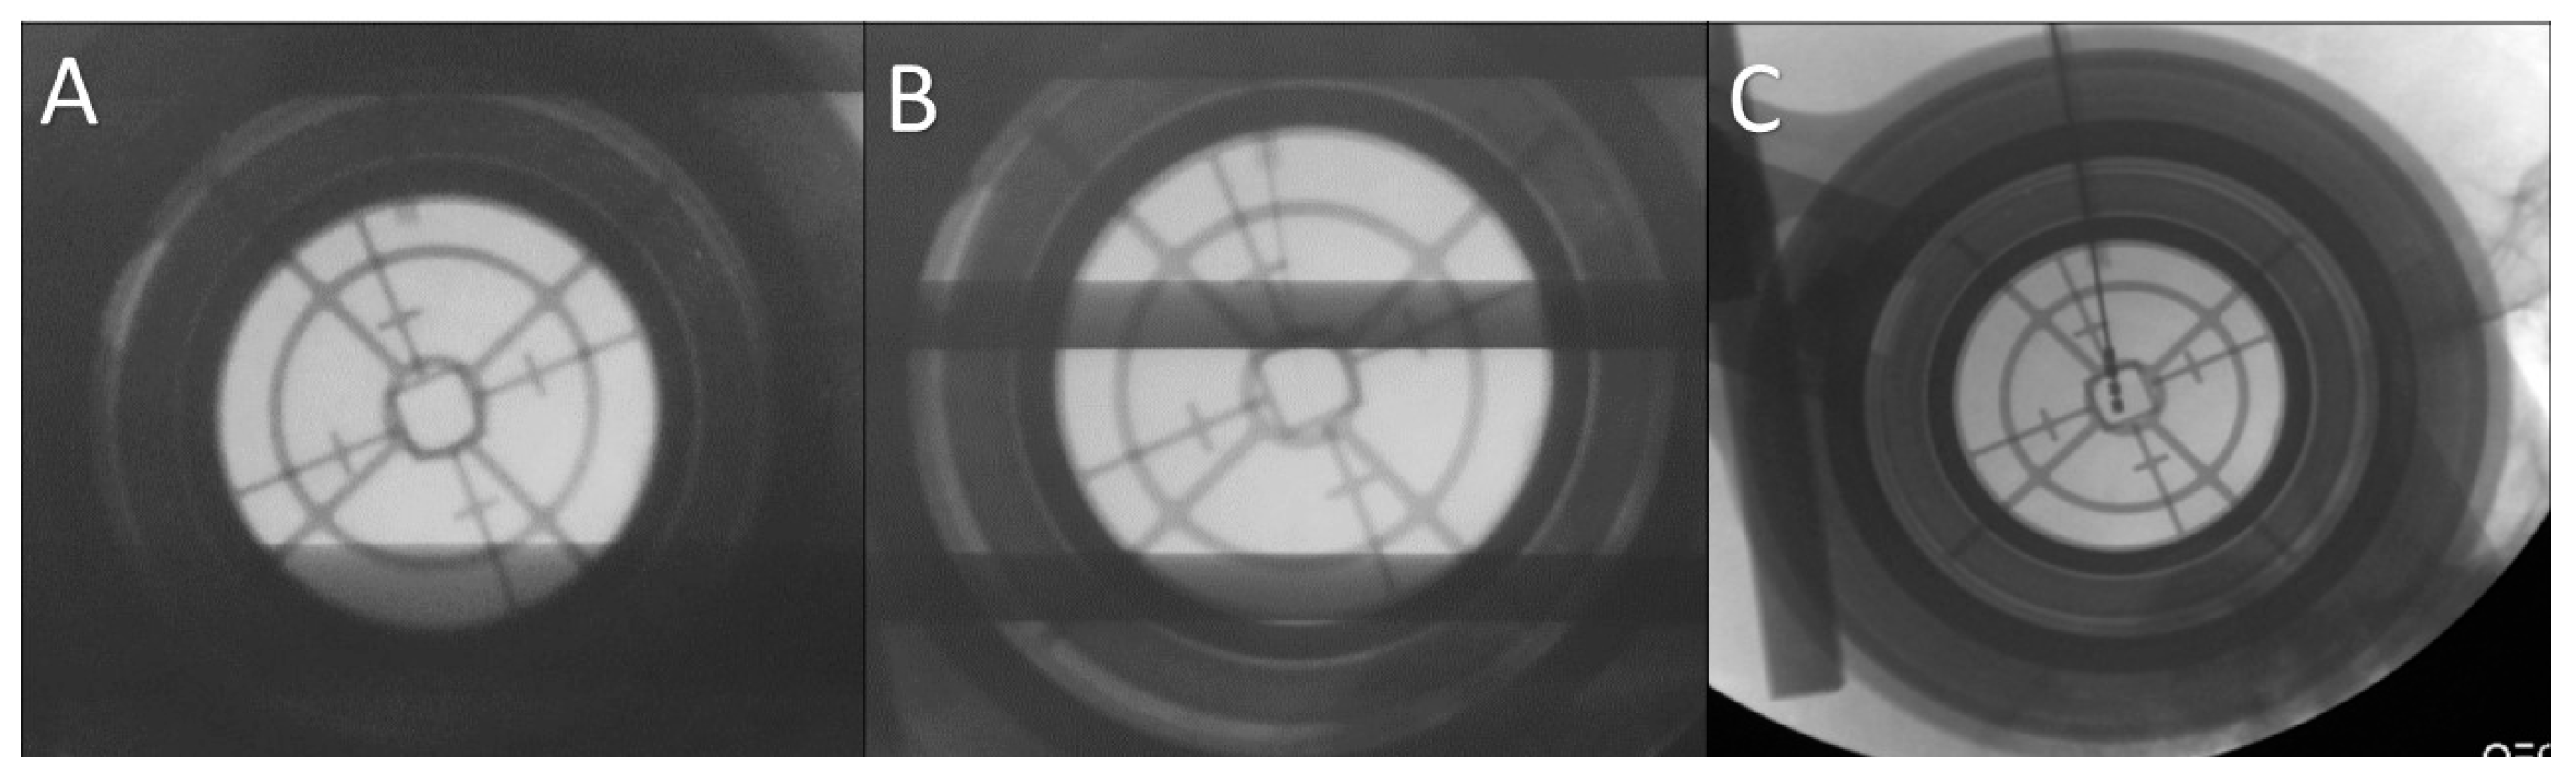

During surgery, we performed microelectrode recording (MER) of the brain activity using a NeuroNav microelectrode recording system (AlphaOmega, Nazareth, Israel). Fluoroscopic confirmation of the target approach was obtained at 5 mm intervals, 2 mm above the target, and at the target (Figure 6).

Figure 6.

Fluoroscopic confirmation of the target approach. (A) Confirmation of the position of the stereotactic cannula; (B) the microelectrode is advanced to the target under fluoroscopic guidance; (C) the final position of the deep brain stimulation (DBS) electrode confirmed.

We tried to minimize the number of the tracks used for recording and stimulation to reach the STN as possible (Figure 6). The maximum number of tracks we used for a single side target was three (Figure 8).

Fluoroscopic confirmation of the electrode position showing (A) a second microelectrode is inserted posterior to the original one due to suboptimal subthalamic nucleus (STN) signal during mapping along the original trajectory; (B) the final position of the deep brain stimulation (DBS) electrode in the new posterior trajectory.

Once we reached our desired target, we removed the microelectrode and replaced it with a standard four contact (0–3) deep brain stimulation electrode (Medtronic DBS lead 3389). Generally, we placed the deepest electrode contact (0) at or just beyond the target point. Then, we repeated the testing using this electrode in order to confirm the reproducibility of the beneficial effects and high thresholds for the undesirable effects (Figure 6 and Figure 8). We locked the electrode in place using a Stimloc device (Medtronic, Minneapolis, MN, USA). Then, the same procedure was repeated again for the opposite side electrode.